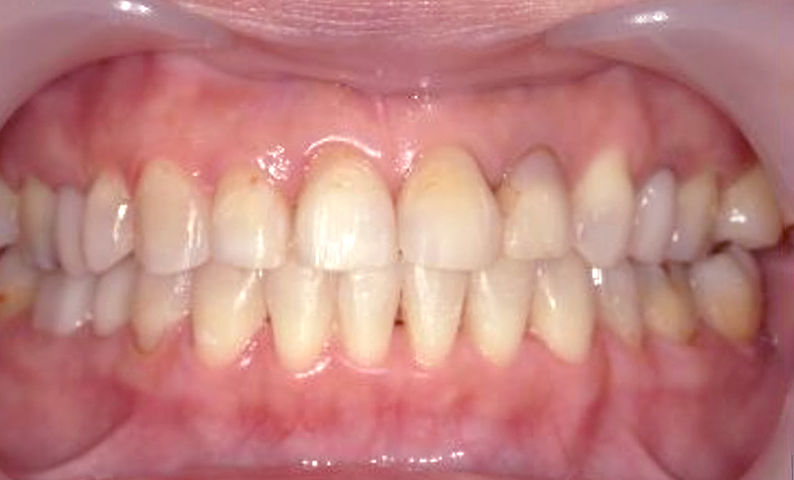

症例_003 下顎だけの部分矯正

治療期間:10ヶ月金額:24万円+税女性前歯のガタガタ下の前歯だけ上顎は補綴治療中